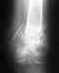

так выглядит моя рентгенограмма, что можете сказать и посоветовать? Заранее благодарен.

Кликните для загрузки файла IMG.jpg

9KB (9689 bytes)

это рентгенограмма через 3 месяца после операции

Кликните для загрузки файла IMG_0001.jpg

14KB (14516 bytes)

Не надо отправлять картинки по 2 мб с разрешением 2500 на 3500 пикселов. При отправке сообщения внимательно читайте, что написано про картинки. Черно-белое полутоновое изображение ~1024x768 пикселов приемлемого качества имеет размер ~10-30 Кб, то есть в 50-100 раз меньше. Иной раз приходится открывать сайт через мобильный телефон, и мегабайтные приложения сильно огорчают.

И что обидно, картинка была 8 мегапиксельная, а качество низкое, изображение нерезкое, да и сам исходный снимок оставляет желать лучшего.

Надо бы доснять трехчетвертные проекции, а то почти вся зона стыка на обеих проекциях перекрыта металлом.

Из того, что удается разобрать - вполне ожидаем рецидив проблемы, то есть несращение с разрушением пластинки.

Пластинка для такого типа перелома - плохой выбор, . Весь мир использует для таких переломов внутрикостный стержень, запертый винтами. Стержень вводится без разреза над переломом. Идеально это сделать и сейчас. Сразу возможна полная нагрузка, в силу механики фиксаторов пластина или винты при несращении ломается, стержень нет, и фрагментам деться некуда - он могут только сближаться по стержню. Так что есть смысл сделать такую операцию и сейчас.